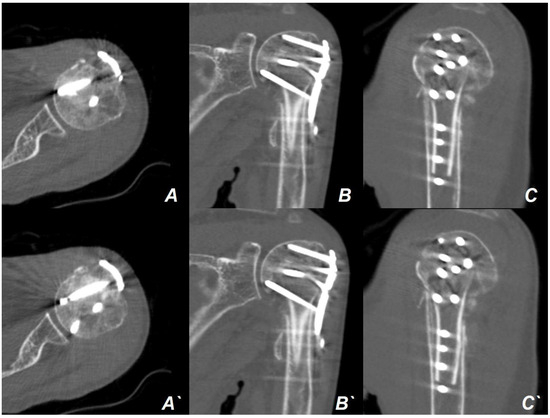

2. Case Presentation

Surgical Technique